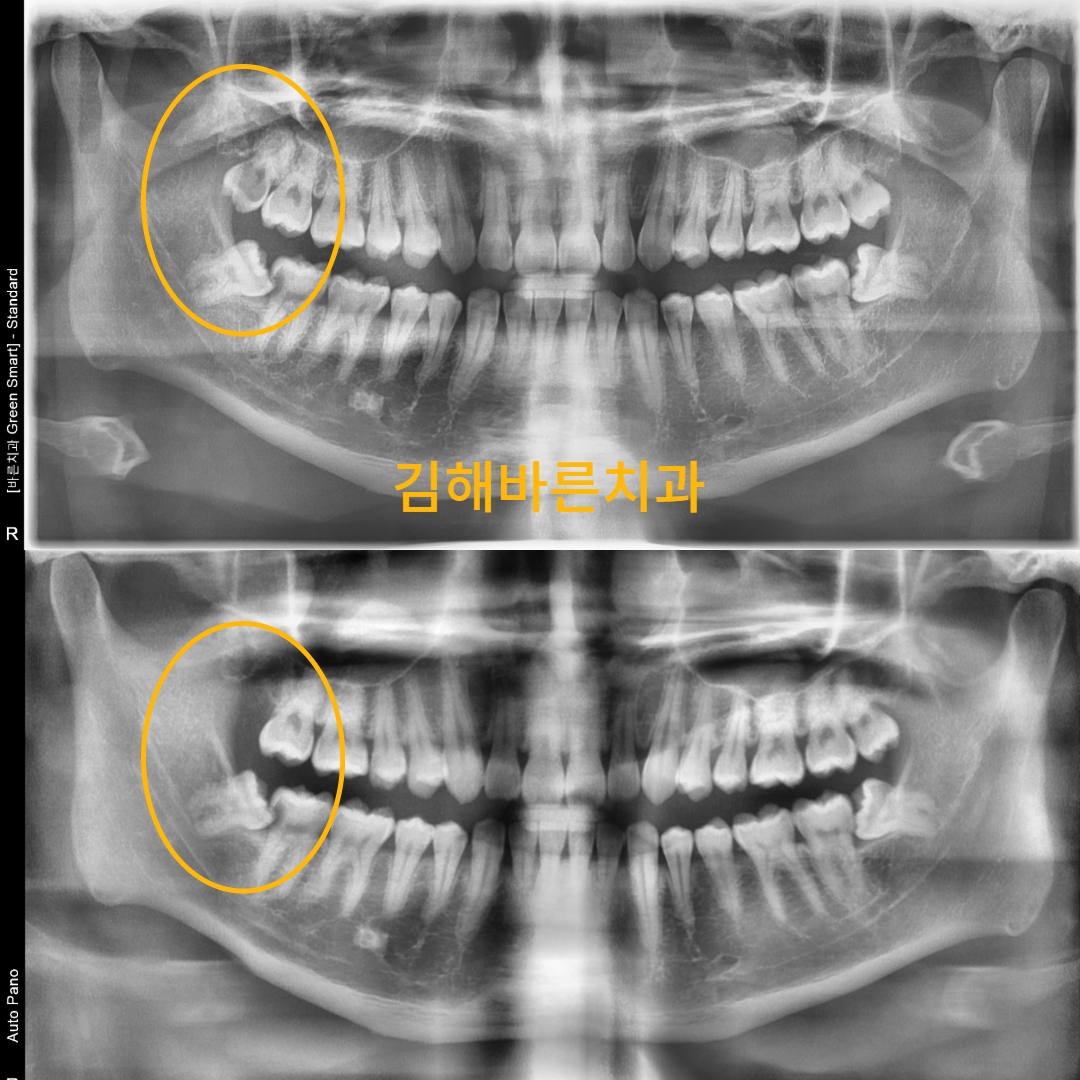

김해바른치과의원

김해바른치과의원 대표 이미지

치아를 가급적 살리기 위해 노력한다는 철학이 인상적이었던 곳이에요. 통증을 최소화하는 마취와 스케일링 시스템이 있다고 해서 저처럼 겁이 많은 사람도 안심하고 갈 수 있겠더라고요. 특히 임플란트 시술 후에는 3차원 CT로 직접 확인시켜준다는 점이 믿음을 주네요.

#무통마취잇몸신경치료#매복사랑니발치#잇몸치료잘하는곳#임플란트보증제

잇몸치료는 물론 임플란트, 사랑니 발치, 충치치료 등 다양한 진료를 전문적으로 한다고 해요. 많은 환자를 보는 공장식 진료가 아닌, 한 명 한 명에게 귀 기울이는 점도 좋았어요.